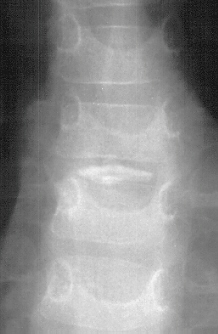

CASE HISTORY

Patient is a 4 year old male who developed the insidious onset of neck pain and stiffness 4 days prior to admission. Over the intervening period, the patient suffered from worsening of his symptoms which led to increasing irritability and difficulty sleeping. On the day of admission, he was seen by a local pediatrician for severe neck pain. It was observed that his head was in a fixed position just slightly right of midline. The patient's past medical history was remarkable for two recent self-limited episodes of hives and urticaria on his trunk and extremities that was treated with prednisone. There was vague history of remote trauma about one month previously when the patient had been "horsing" around with his brother. The child had no evidence of a viral prodrome, constitutional symptoms or travel history. He was sent to a local hospital where radiographs of the cervical spine demonstrated calcifications in the C3-4 and C5-6 intervertebral disc spaces . Neurological exam was normal. The child's pain was refractory to morphine treatment and he was transferred to A.I. for the management of his intractable pain. On arrival, his physical exam was unchanged. Blood work revealed a WBC count of 12.7K with 75% PMNs and an ESR of 80. Radiographs of spine showed the presence of an addition calcification in his thoracic spine . He was treated with oral valium and a soft cervical collar. Over the ensuing 24 hrs the child demonstrated marked improvement of his symptoms and was switched to motrin. He was subsequently discharged.

XRAYS

The number of calcified discs varied from 1 to 12 (mean 1.69) . Symptomatic calcified discs are most common at C6-7. Radiologic examination shows images of calcium density in the normally radiolucent intervertebral discs. Anterior or posterior protrusion can be observed. The lesions demonstrate high density on CT and low signal intensity on MRI.